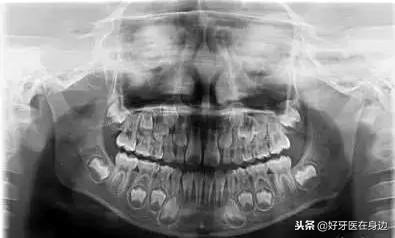

2.换牙期间一定要带宝宝去做一下的牙齿的体检,拍片子了解牙齿的发育情况,并及时进行干预处理!

全景片可以看到牙胚的情况